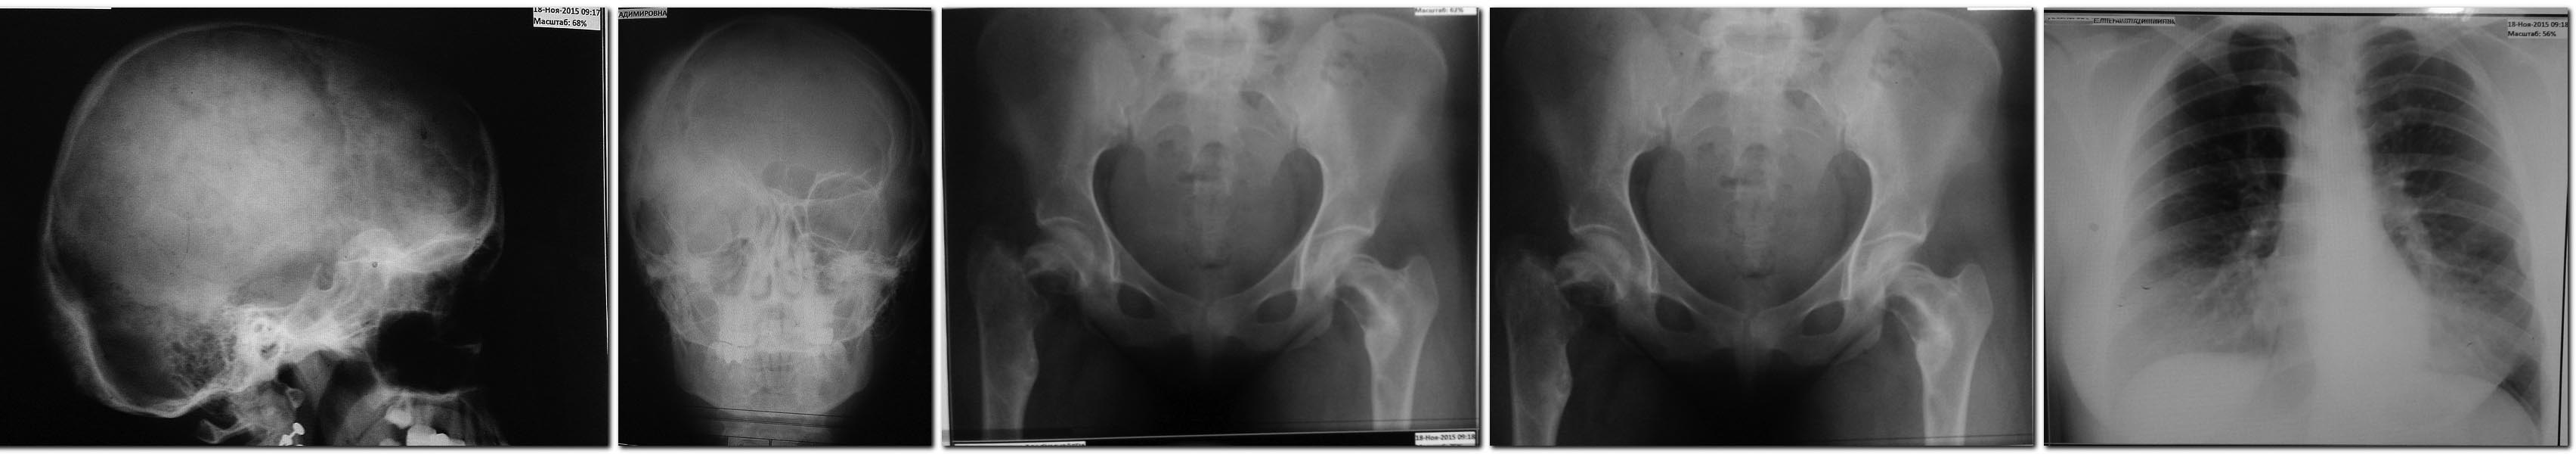

Травму отрицает, оступилась при ходьбе, острая боль в паху. Не смогла далее опираться на ногу. На р-грамме (приложена) - патологический перелом бедра на фоне выраженного остеолитического процесса. Кроме того, обнаружена крупноячеистая кистозная перестройка в контрлатеральной шейке бедра и вертельной зоне. На р-грамме грудной клетки кистозно перестроены грудинные концы ключиц.

Р-грамма черепа- периостальная реакция на фоне кистозной перестройки в области затылочного бугра, сосцевидных отростков, деформированы контуры глазниц.